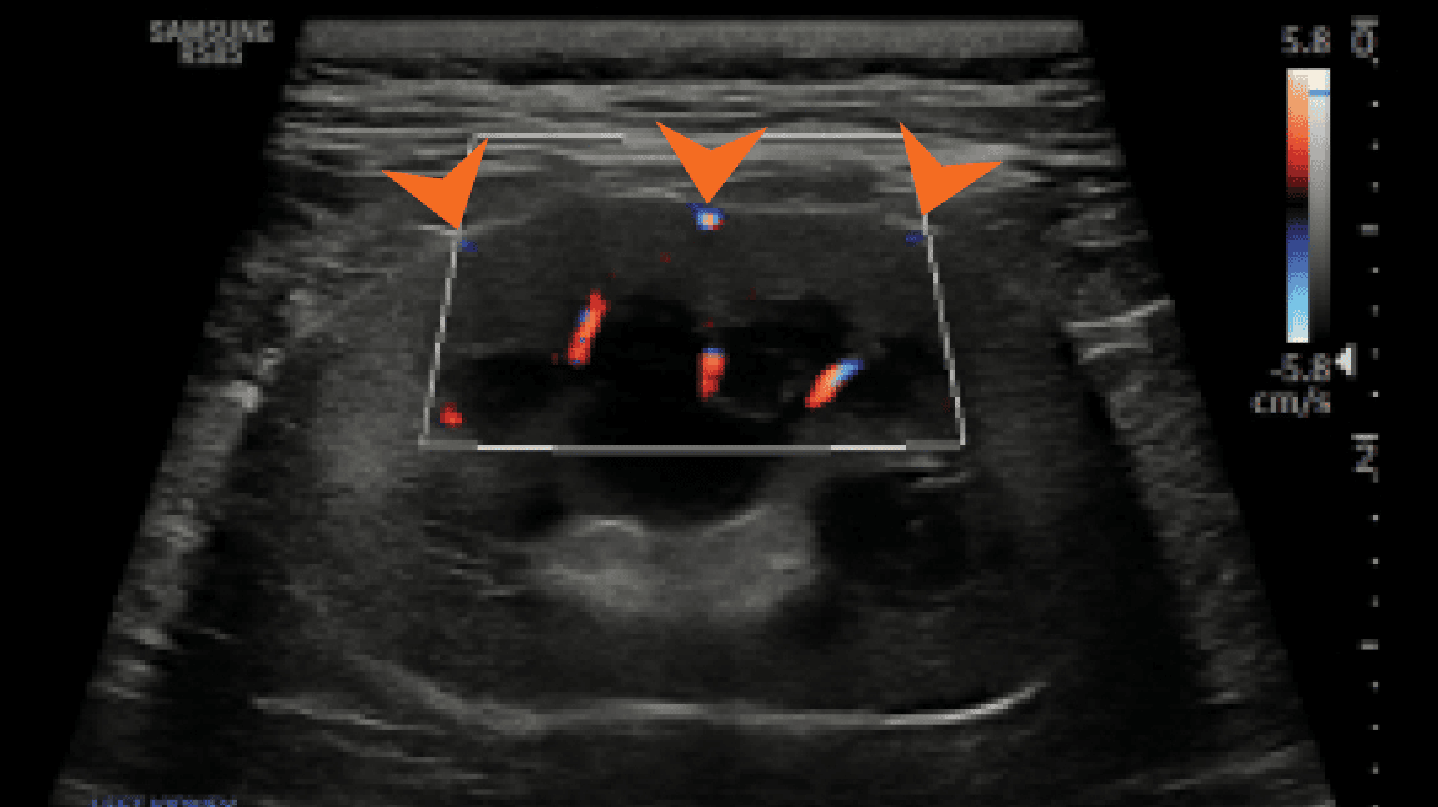

Prawidłowy obraz ultrasonograficzny nerek został szczegółowo omówiony w innych źródłach,7 a poniższy artykuł koncentruje się na przewlekłej chorobie nerek u kotów i psów. Nerki powinny być obrazowane w trzech projekcjach – strzałkowej, dogrzbietowej i poprzecznej (ryc. 1).7 U psów, zwłaszcza małych ras, opisano obecność hiperechogenicznego zewnętrznego pasma rdzeniowego, które obserwuje się z umiarkowaną częstością u pacjentów bez stwierdzonej choroby nerek (ryc. 2).8 U kotów kora nerek może być jednorodnie silnie hiperechogeniczna ze zwiększonym w następstwie zróżnicowaniem korowo-rdzeniowym wtórnym do lipidozy kanalików bliższych (ryc. 3).9 Odkładanie się tłuszczu w kanalikach nerkowych jest konsekwencją otyłości bez jednoczesnego upośledzenia czynności nerek.10 Dodatkowo rutynowo obserwuje się zależny od kąta badania artefaktowy wzrost hiperechogeniczności kory i rdzenia nerek, wtórny do anizotropii, w obszarach, w których kanaliki nerkowe ułożone są prostopadle do płaszczyzny fali ultradźwiękowej. Na przykład podczas obrazowania nerki w projekcji strzałkowej echogeniczność biegunów doczaszkowego i doogonowego będzie ogniskowo i artefaktowo zwiększona (ryc. 4).11 Z doświadczenia autorów wynika, że łagodna nieregularność brzegów nerek, szczególnie u kotów, może być obserwowana w miejscach, gdzie naczynia nerkowe przebiegają wzdłuż torebki nerkowej, i nie powinna być błędnie interpretowana jako zmiana zwyrodnieniowa (ryc. 5). W lokalizowaniu tych naczyń użyteczna jest ultrasonografia dopplerowska kodowana kolorem lub w trybie mocy.

Medium huguet ryc5 opt

Ryc. 5. Badanie ultrasonograficzne metodą dopplera mocy lewej nerki kota, ukazujące równomiernie nieregularne brzegi w miejscach, gdzie naczynia nerkowe przebiegają wzdłuż torebki nerki (groty strzałek).